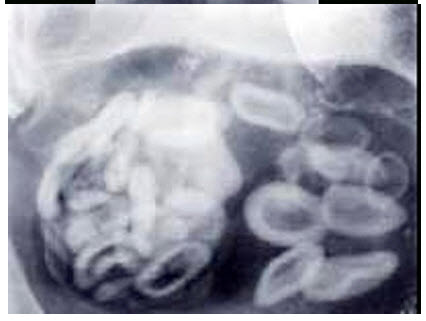

109、单项选择题

女,30岁,喜欢吃柿子,近日出现腹痛,腹胀,X线检查如图,最可能的诊断是()

A.骶骨肿瘤

B.钡餐检查后钡剂残留

C.肠结石

D.盆腔异位肾钙化

E.盆腔畸胎瘤